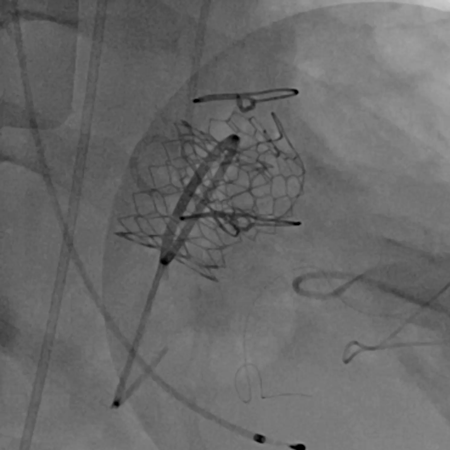

黄焕雷主任带领具有丰富经验的心脏麻醉医师、体外循环师、超声心动图医师、手术室、心外重症监护室、心脏导管室多学科团队,联合心内科专家谢年谨主任,为蔡先生实施小切口下、介入途径的主动脉瓣“瓣中瓣”、二尖瓣“环中瓣”的同期植入手术:黄主任首先在患者左前胸做一小切口,暴露患者的心尖,在跳动的心脏上“绣”上荷包作为介入导管、瓣膜的植入“门户”;随后,黄焕雷主任在超声心动图、放射透视的引导下,将一钢针在患者心尖“扎”入患者心脏内,为之后的瓣膜植入作为引导,具体来说就是将预先选择适合患者大小的生物瓣膜折叠、压缩入细长的输送管道内,好比将瓣膜这一“弹头”安放在输送导管这颗精准制导的“火箭”上,而黄主任的双手则控制这一精准发射和制导,再将瓣膜输送到主动脉合适的位置后释放,新的主动脉瓣便牢固地“卡”在了原有的主动脉瓣架内。经过透视和超声心动图评估,主动脉瓣位置合适,开放、闭合功能良好。随后,黄主任通过这一根钢针和输送导管,利用类似的方式,调整“火箭”的发射轨道,在原有二尖瓣人工瓣环内植入预先选择好大小的二尖瓣生物瓣膜,经过影像学方式评估,新植入的二尖瓣生物瓣工作良好。

球扩释放主动脉瓣瓣中瓣